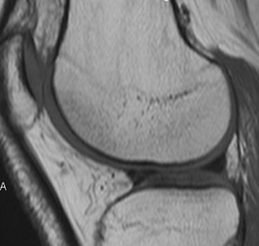

Fig 32. Ligamento transverso normal.

A: RM sagital en T1 y B: RM axial en T2. Estructura hipointensa en todas las secuencias, que une los meniscos en su parte anterior.